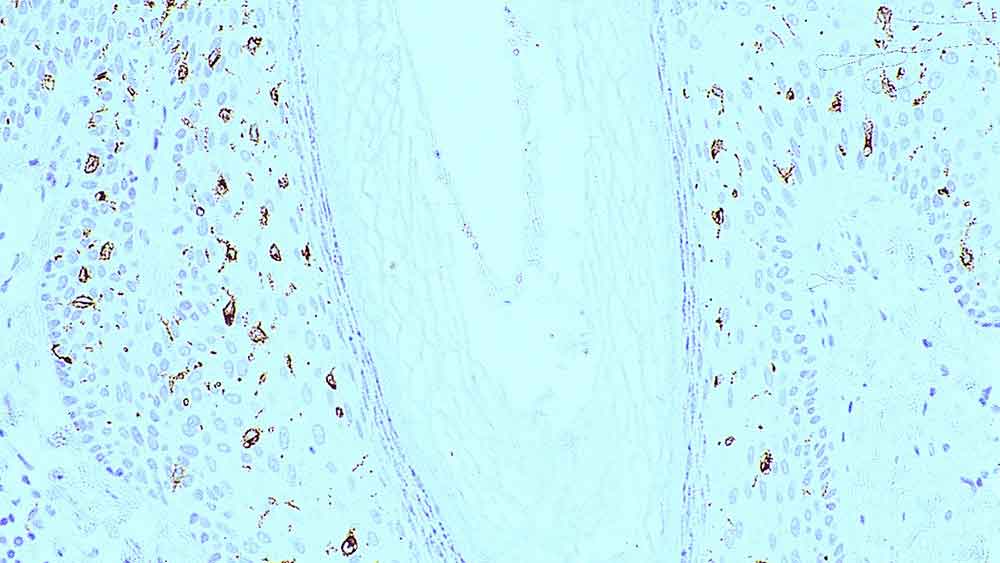

Human colon, ulcerative colitis: immunohistochemical staining for CD16. Note intense membrane staining of infiltrating natural killer cells, granulocytes and activated macrophages. CD16: clone 2H7

CD16 antigen has a molecular weight of 50 to 70 kD and is a low affinity Fc receptor for complexed IgG, Fc/gamma RIII, expressed on natural killer (NK) cells, granulocytes, activated macrophages and a subset of T cells expressing alpha-beta or gamma-delta T cell antigen receptors. The CD16 antigen exists both as a glycosyl-phosphatidylinositol (GPI)-anchored protein in polymorphonuclear cells and as a transmembrane protein in NK cells.